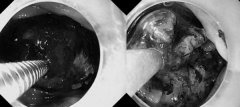

• 男子贪吃雪花山楂胃里长结石!医生提醒

• 女子吃了30多颗,痛到无法忍受,可乐成“解药”!重庆网友:第一次听说……

胃结石 山楂 江女士 2024/11/22

• 空腹吃山楂胃里长结石?秋天吃柿子容易胃结石?医生提醒

胃结石 柿子 山楂 2024/10/31

• 女子吃了“1米长”冰糖葫芦,竟长出巨大胃结石

李女士 山楂 冰糖葫芦 2024/12/26